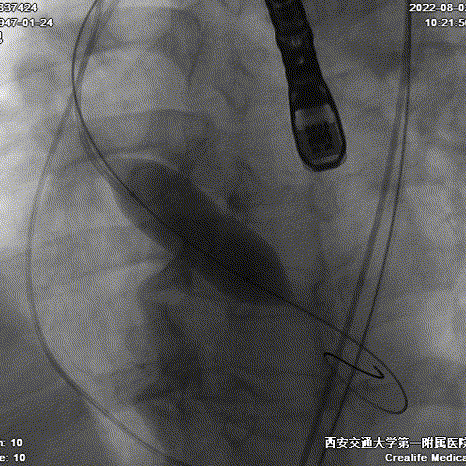

递送到达释放位

Type0型二叶瓣伴偏心性钙化导致瓣膜定位困难,如果释放位置偏浅,瓣膜蹦出风险高。术者利用Evolut PRO稳定的多次可回收功能,通过调整瓣膜植入深度,确保瓣膜流入端稳固锚定在瓣环根部。通过造影评估,瓣膜植入位置理想,因此进行过最后缓慢释放,瓣膜顺利达到目标植入深度。

首次释放

二次释放